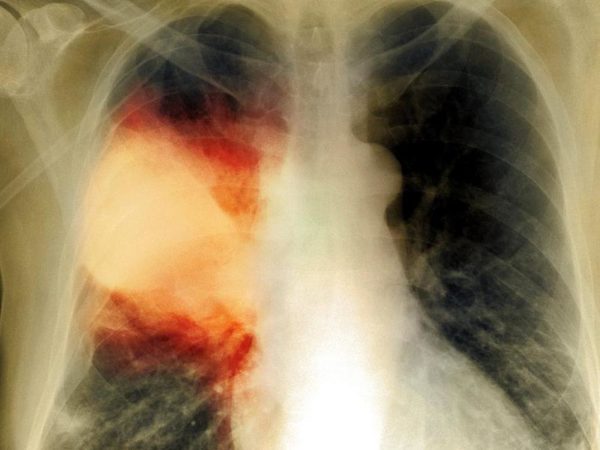

Инфильтрация – это наличие воспалительной жидкости, которая состоит из продуктов крови, белков, клеток организма и бактерий, в просвете альвеол. Данная инфильтрация хорошо видна при проведении рентгенологического исследования и слышна врачу в виде специфических хрипов при выслушивании легких. Также пневмония сопровождается признаками воспаления, в том числе интоксикацией и повышением температуры, кашлем с возможным отхождением мокроты и другими симптомами.

Прежде всего, диагноз пневмонии устанавливается по результатам обследования, которое назначает и проводит лечащий врач. Подозрение на пневмонию должно возникнуть у пациента с длительным повышением температуры, кашлем с отхождением кровавой или ржавой мокротой, болью в грудной клетке, сильной слабостью и одышкой. Единственным видом обследования, после проведения которого можно говорить об определенном диагнозе пневмония – это рентгенография или КТ легких.

При подозрении на пневмонию, скорее всего, врач назначит проведение рентгенологического исследования легких, клинический анализ крови, возможно врач попросит вас сдать мокроту на анализ, и назначит биохимические исследования, в том числе на показатели воспаления – С-реактивный белок или прокальцитонин. В сложных случаях, может потребоваться проведение компьютерной томографии легких, и бронхоскопии.

Клинические проявления пневмонии и изменения на рентгенограмме могут сохраняться в течение месяца. При неосложненном течении, на фоне терапии антибиотиками, улучшение самочувствия будет уже в первый день. Обычно, лечение назначается на 7-10 дней, иногда, антибиотики приходится принимать 3-4 недели. Через 1 неделю к пациенту вернутся силы и хорошее самочувствие. Однако, полное выздоровление наступает через месяц от начала болезни, до этого времени, пациент может ощущать слабость, покашливание, периодически может подниматься температура. Если в течение первого месяца пневмонии сделать рентген легких, то, скорее всего, будут выявлены изменения, которые могут трактоваться как пневмония. Однако, это не всегда значит, что лечение не помогает или пневмония не проходит, изменения на рентгенограмме могут сохраняться в течение месяца от начала терапии.